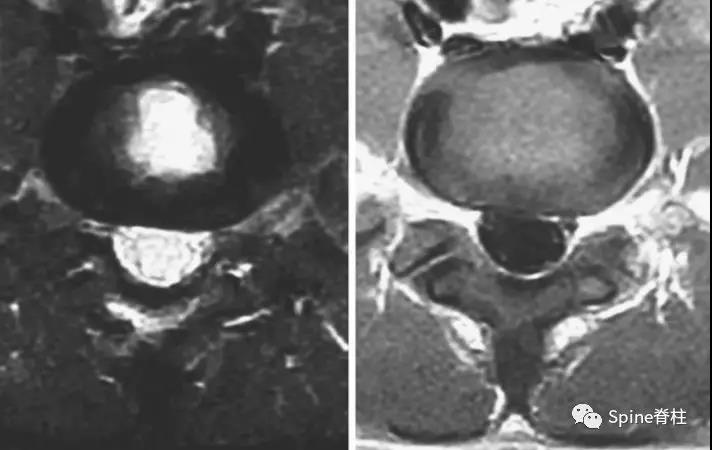

图:15岁腰痛男孩,左侧腰5椎弓根裂A:T1左侧腰5椎弓根低信号(箭头);B:T2左侧腰5椎弓根高信号(箭头);C:T2轴位左侧腰5椎弓根骨折线明显,伴高信号区(箭头)